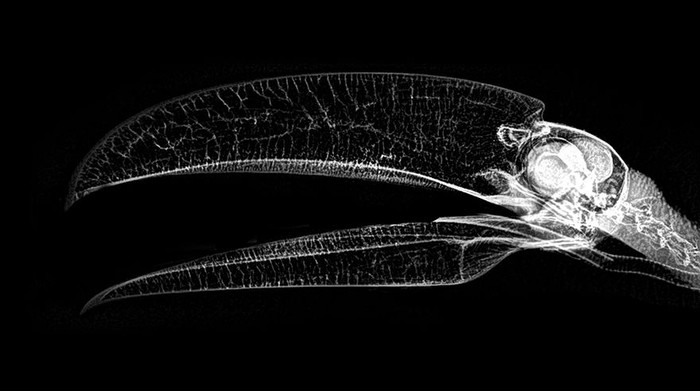

Jakarta - Kebun binatang London dan Oregon merilis foto X-Ray sejumlah hewan-hewannya. Foto tersebut kerap digunakan untuk memantau kondisi kesehatan para hewan.

Deretan Foto X-Ray Para Hewan